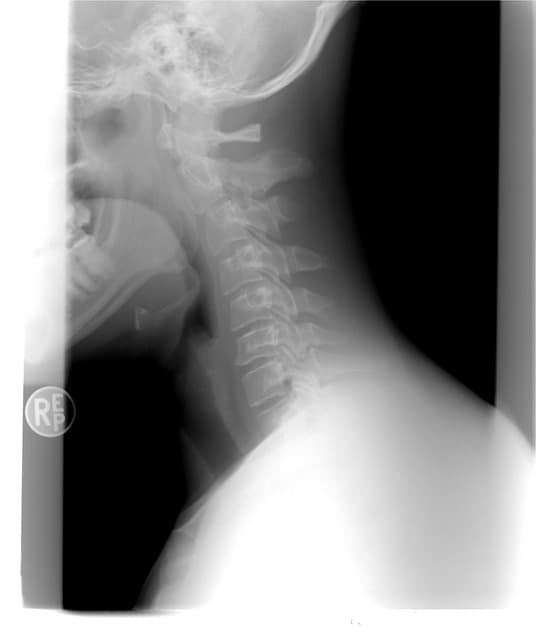

갑상선 목부음

주변을 둘러보면 갑상선에 대한 질병을 흔하게들 많이 들어보셨거나 볼 수 있으실거에요. 한편 갑상선은 우리 목에 위치해 있는데요. 한편 신진대사에 필요한 갑상선 호르몬을 분비하는 내분비기관을 말하는 것으로 전해지고 있는 것으로 파악되고 있습니다.

각종 대사에 필요한 호르몬이기 때문에 갑상선은 매우 중요하죠. 한편 하지만 갑상선 목부음 증상을 느끼시는 분들이 많이 계실텐데요. 더불어 세포성장이 과하게 이루어지거나 할때 갑상선에 종양이 생겨서 갑상선 목부음이나 이물감을 느낄 수 있는 것으로 파악되고 있습니다. 갑상선에 불편함을 느끼고 종양이 생기는 것은 전세계적으로 약 5%정도 가지고 있다고 하는 것으로 알려져 있는 것으로 보여요. 한편 개개인에 따라 갑상선이 위치도 다르고 개수나 크기도 다르고 갑상선 목부음 증상도 다르게 나타난다고 하는 것으로 알려져 있는 것으로 보여요. 갑상선 목부음은 갑상선종으로 불리우는데요. 한편 이게 크기가 커지거나 통증이 심해지면 숨을 쉬거나 음식을 삼키는데 불편함이 생겨 일상생활속에서 많은 불편함을 느낄 수 있다고 하는 것으

로 알려져 있는 것으로 보여요. 갑상선 목부음 증상은 갑상선 호르몬이 과도하게 생산되거나 반대로 너무 적게 생산되서 생길 수 있다고 하는데요. 한편 갑상선 호르몬 과다 분비의 경우 갑상선 기능 항진증이라고 불린답니다. 갑상선 기능 항진증의 증상으로는 긴장감을 자주 느끼게 되고 심계항진이라고 하여 자기 심장박동을 느낄 수 있는 것으로 파악되고 있습니다. 한편 이외에도 과잉활동으로 증상이 나타날 수 있으며 땀을 많이 흘리거나 열에 민감해 질 수 있는 것으로 파악되고 있습니다. 한편 이외에도 피로감을 느끼거나 모발 손실과 체중감소로 이어지기도 하는 것으로 전해지고 있는 것으로 파악되고 있습니다. 한편 갑상선 기능 항진증은 그레이브스병에 의해서 발견하게 되는 것으로 보입니다. 갑상선이 커지고 붓는것이 갑상선 호르

몬이 부족해서 생길 수도 있는데요. 한편 이때는 추위를 많이 타게 되거나 변비가 생기고 기억력 감퇴나 체중증가 등의 증상이 나타나게 되는 것으로 보입니다. 한편 갑상선 기능 저하증은 뇌하수체에서 갑상선 자극 호르몬을 분비하여 갑상선이 자극을 받게 되는데 이러한 자극이 갑상선을 붓게 만든다고 하는 것으로 전해지고 있는 것으로 파악되고 있습니다. 이러한 증상이 생기는것은 다양한 이유로 인하여 나타날 수 있는데요. 한편 첫번째 이유는 바로 요오드 결핍때문것으로 알려져 있는 것으로 파악되고 있습니다. 한편 요오드 결핍은 갑상선이 부워서 커지는 가장 흔한 원인인데요. 한편 갑상선 호르몬을 생산하기 위해서 필요한것이 바로 요오드 인데 이러한 요오드가 부족함으로써 갑상선종이 많이 발생하게 되는 것으로 보입니다. 요오드 결